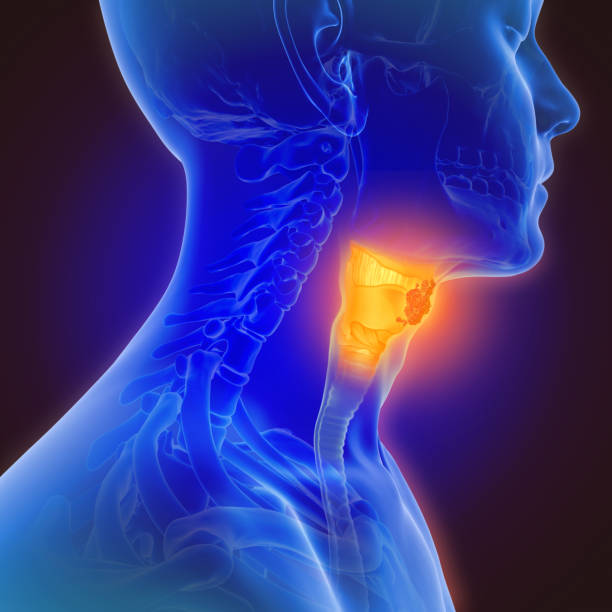

인후두 역류 질환

인후두 역류 질환은 위산이 인후두까지 역류하여 염증을 일으키는 질환입니다. 이 질환은 식도역류와 비슷한 증상을 보이며, 특히 목이 간질간질하고 마른 기침이 나타날 수 있습니다. 인후두 역류 질환 환자는 목의 염증과 마찰로 인해 간질감이 생겨, 기침을 할 때 목이 간질하고 마르게 느껴지는 것입니다.

또한 인후두 역류 질환은 트라우마나 중성지방, 당뇨, 흡연, 알코올 등 다양한 요인에 의해 발생할 수 있으며, 식습관 개선과 약물 치료를 통해 증상을 완화시킬 수 있습니다. 인후두 역류 질환은 만성적으로 발생하면 위암 등의 합병증을 유발할 수 있으므로, 조기에 의학적인 상담과 치료가 필요합니다. 증상이 나타날 경우 의료진의 상담을 받아 적절한 검사를 시행하고, 증상의 원인을 파악하여 적절한 치료 방법을 선택하는 것이 중요합니다.